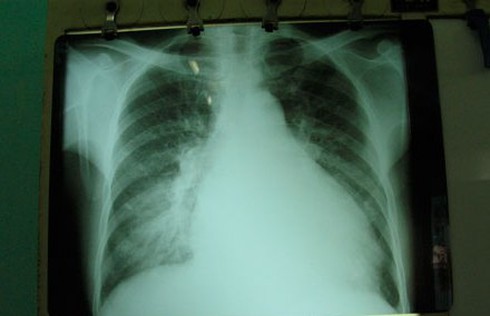

Bác sĩ CK II Vũ Đức Chung, Trưởng khoa Nội Tiêu hóa, Bệnh viện 354 cho biết, anh H. nhập viện với triệu chứng loạn thần do cai rượu. Khi kiểm tra thăm khám và xét nghiệm thì bệnh nhân còn bị xơ gan và đặc biệt khi chụp XQuang phát hiện tim bệnh nhân to như trái bầu (gấp hơn 1,5 lần so với bình thường), kết quả xét nghiệm suy tim.

| Hình ảnh Xquang quả tim "khổng lồ" của anh H. |